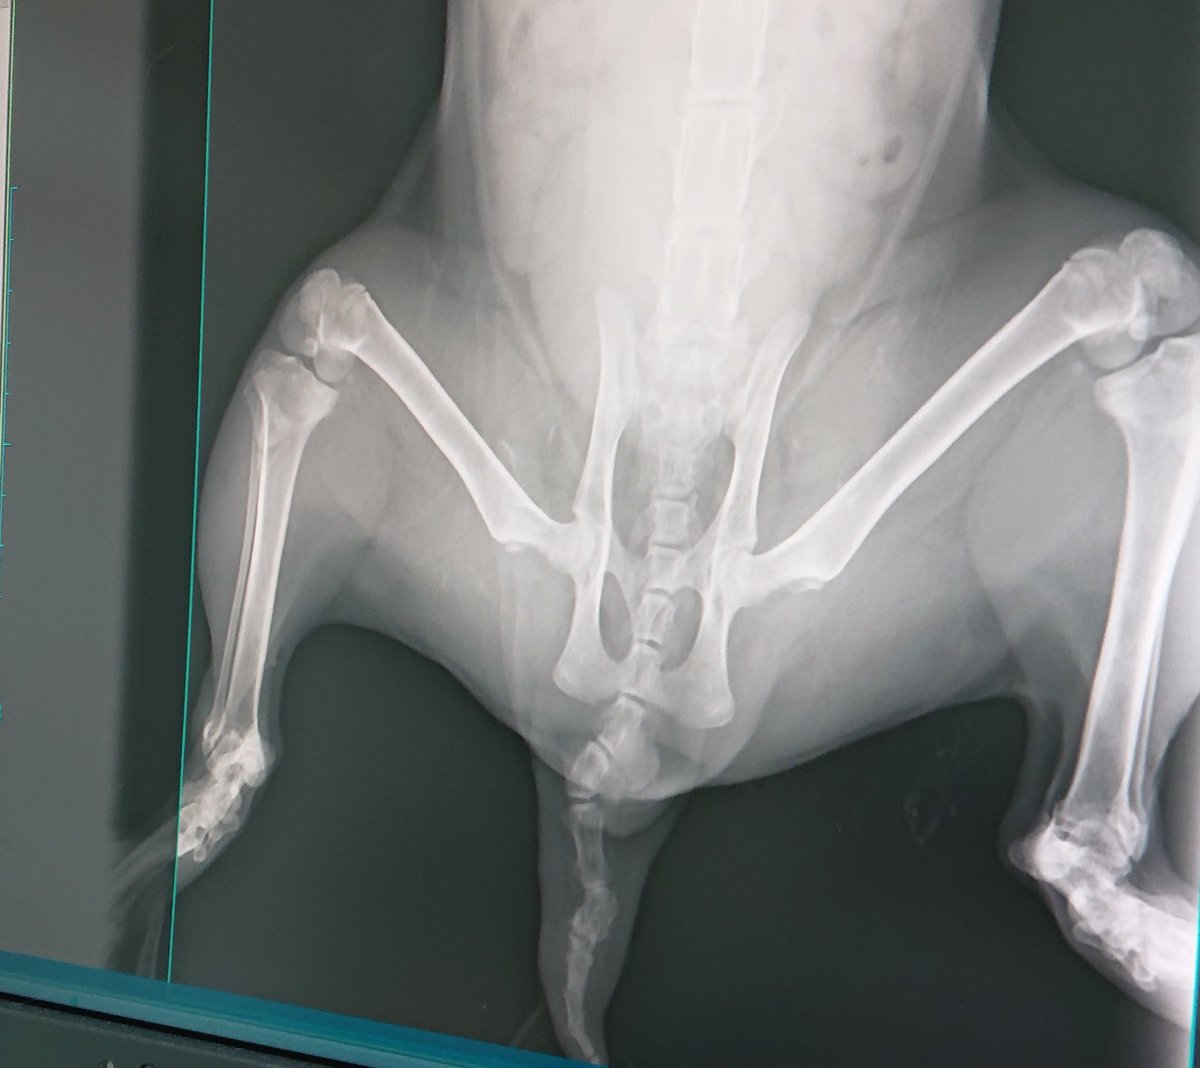

飼い主さんの事情より里親さんを募集します。福岡近隣で犬の扱いに慣れていらっしゃる方 【名前】ゆら 【性別】メス 【種類】雑種 【年齢】推定3歳 穏やかな性格ではありますが、 物音(雨や雷、雷の光、風の音)が苦手で逃亡し骨折して入院中💧 ご質問などあれば 飼い主さんにお繋ぎします。

またもや交通事故の猫。 今回は餌やりさんが病院に行ってくれたはいいけど、骨盤骨折でもう何も出来ないと言われたって。 セカンドオピニオンで、お世話になってるH先生へ、、、 ん~折れてないよ。 お尻と尻尾の傷が爛れてるから消毒しよう( ̄▽ ̄;) やっぱりセカンドオピニオン大切